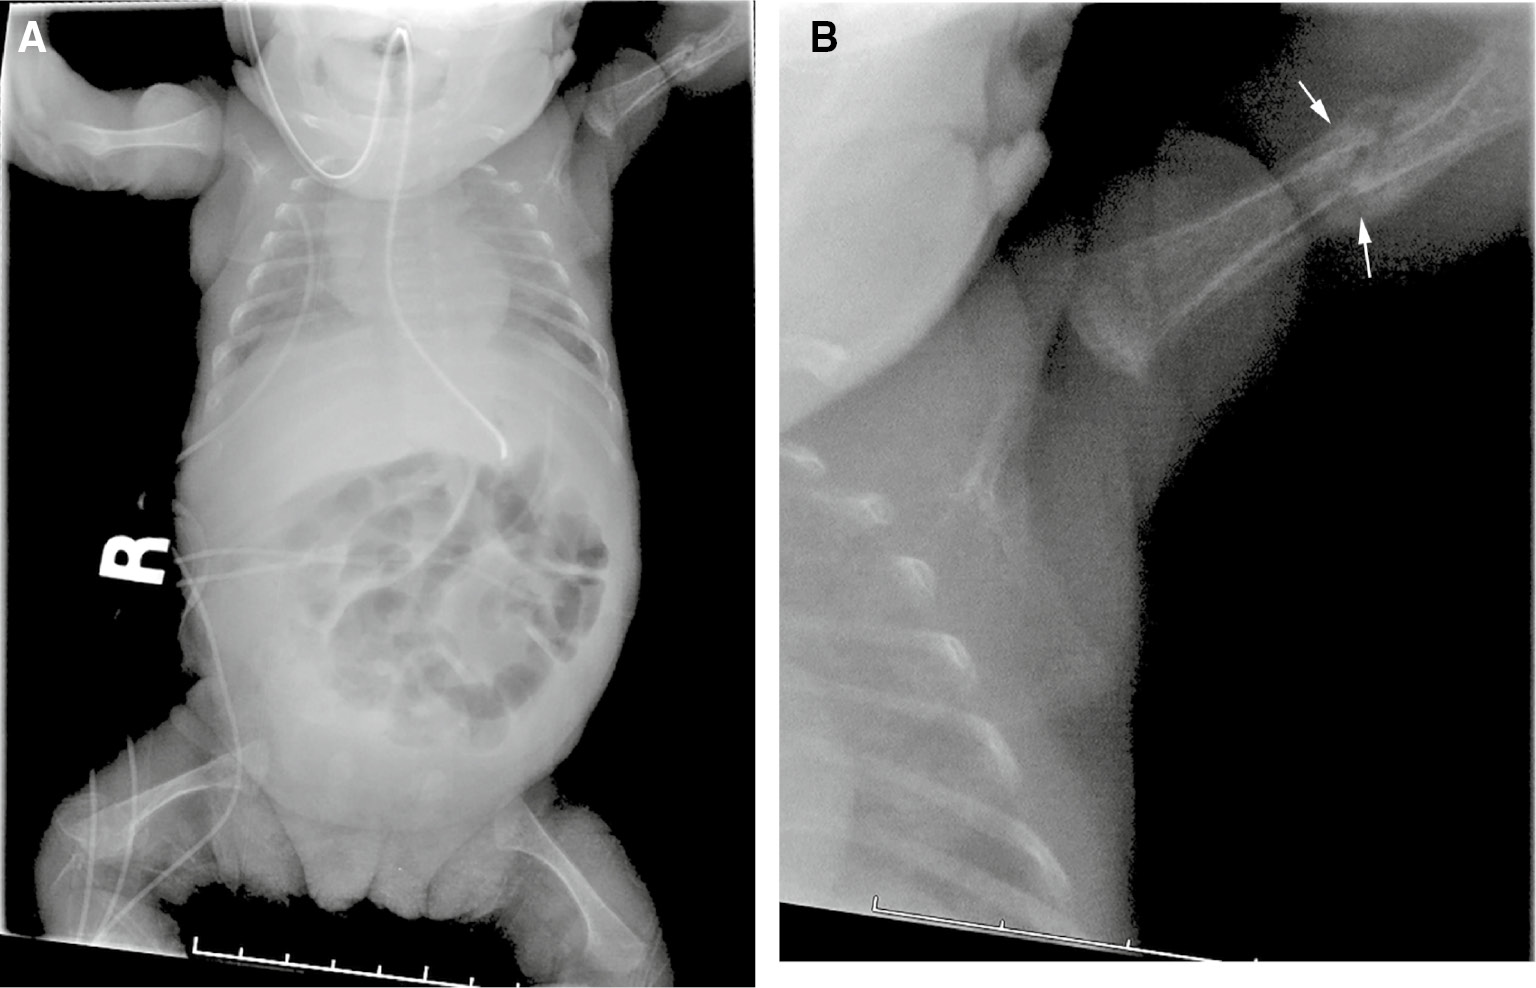

Another form of search satisfaction can be described as “visual isolation”, during which a radiologist’s search pattern is truncated to the main areas of an image, while little or no attention is given to peripheral areas [18]. A clinical example is shown in Figure 2. This chest radiograph was obtained to confirm feeding tube placement in a premature infant with chronic lung disease. Most of the radiologist’s attention is devoted to the location of the tube within the chest and abdomen, and an evaluation of pulmonary inflation and parenchymal opacities that might suggest the presence of atelectasis, pulmonary edema or infection. The evaluation of bony structures and the abdomen are relegated to a lower level of inspection, or ignored. A new left humeral fracture is visible in the periphery of the image, but was not identified on initial inspection.

Figure 2: Visual isolation error.A 2-week-old, former 24-week gestation infant with chronic lung disease. The X-ray was obtained to confirm location of a feeding tube within the stomach. Frontal view of the chest and abdomen (A) shows the feeding tube in adequate position. A healing left humerus fracture (arrows, B) was missed.

Figure 2:

Visual isolation error.

A 2-week-old, former 24-week gestation infant with chronic lung disease. The X-ray was obtained to confirm location of a feeding tube within the stomach. Frontal view of the chest and abdomen (A) shows the feeding tube in adequate position. A healing left humerus fracture (arrows, B) was missed.